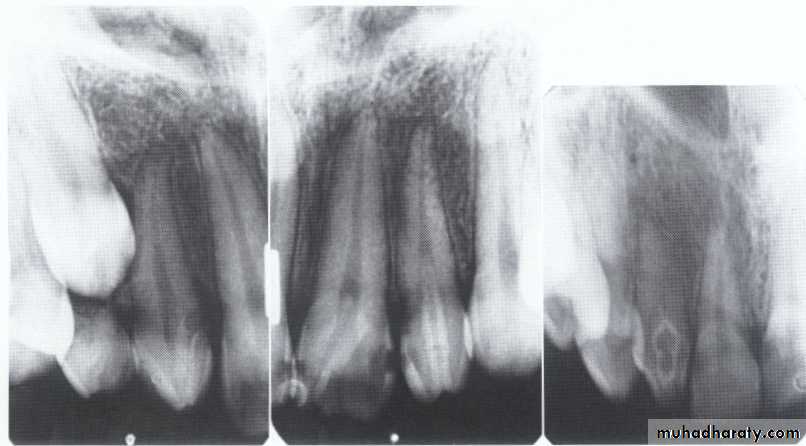

Hypodontia

Oligodontia

Anadontia

Developmental absence of all maxillary premolars and both mandibular second premolars. Note the retention of the maxillary primary canine as a result of the posterior position of the maxillary permanent canine.

CAUSES: may be the result of numerous independent pathologic mechanisms that can affect the orderly formation of the dental lamina (e.g.,orofaciodigital syndrome), failure of a tooth germ to develop at the optimal time, lack of necessary space imposed by a malformed jaw, and a genetically determined disproportion between tooth mass and jaw size.

MANAGEMENT: Missing teeth, abnormal occlusion, or altered facial appearance may cause patients psychologic

distress.

*Mild hypodontia by orthodontics.

*Severe cases by restorative,implant, and prosthetic procedures .